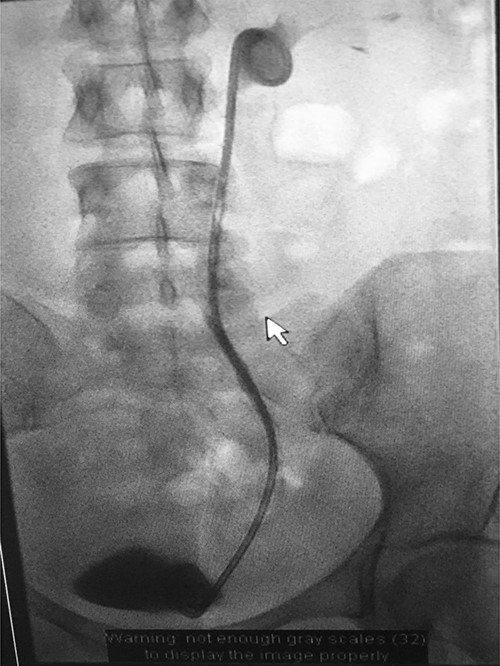

Under conscious sedation, using the previously inserted right percutaneous nephrostomy, antegrade access was achieved into the intrarenal collecting system and then into the proximal ureter. An 8 Fr × 11-cm access sheath was introduced. A guidewire was advanced antegradely through the site of ureteric transection and coiled in a position adjacent to the position of the guidewire that had been inserted retrogradely. A Gooseneck snare catheter was then passed over the guidewire and the snare was inserted (Figs 4 and 5). Under fluoroscopic guidance, the retrograde wire was retrieved and brought externally via the nephrostomy site, achieving through-and-through wire access (Figs 6 and 7).

Fluoroscopic images showing the retrograde wire successfully retrieved and brought externally via the nephrostomy site, achieving through-and-through wire access.